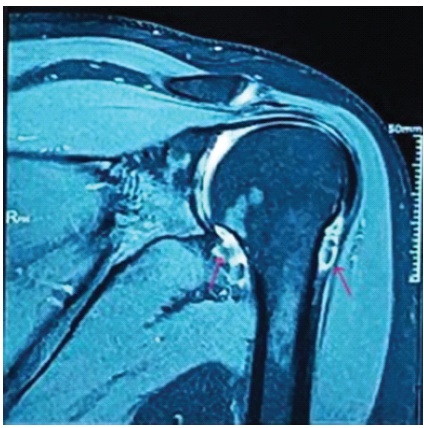

Plain radiography was grossly normal except for some medial calcification. MRI demonstrated multiple loose bodies involving the subscapular recess, posterior and inferior aspect of the glenohumeral joint, and at the rotator interval, suggestive of SCM (Fig. 1).

Figure 1: Pre-operative magnetic resonance imaging (MRI) of left shoulder joint: T2-weighted fat-saturated coronal MRI revealed multiple loose bodies that appeared as numerous focal filling defects, suspended within the hyperintense joint effusion.